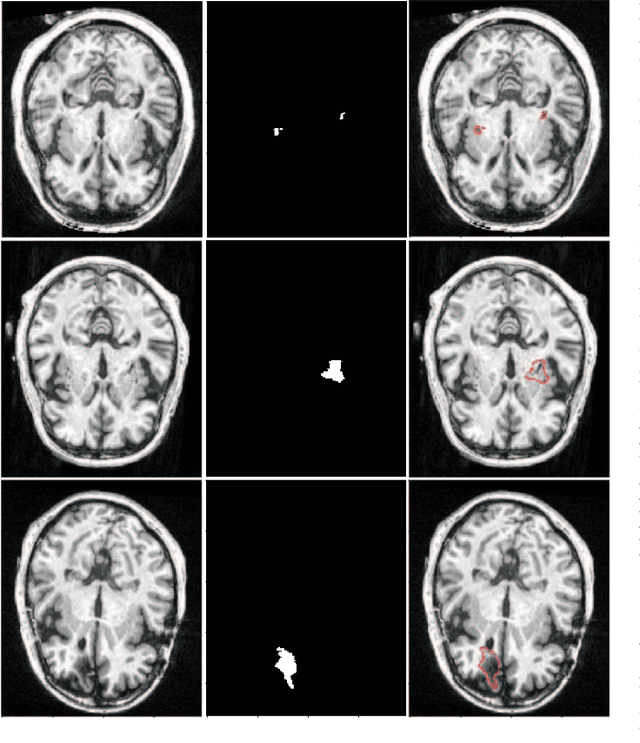

Assessing the location and extent of lesions caused by chronic stroke is critical for medical diagnosis, surgical planning, and prognosis. In recent years, with the rapid development of 2D and 3D convolutional neural networks (CNN), the encoder-decoder structure has shown great potential in the field of medical image segmentation. However, the 2D CNN ignores the 3D information of medical images, while the 3D CNN suffers from high computational resource demands. This paper proposes a new architecture called dimension-fusion-UNet (D-UNet), which combines 2D and 3D convolution innovatively in the encoding stage. The proposed architecture achieves a better segmentation performance than 2D networks, while requiring significantly less computation time in comparison to 3D networks. Furthermore, to alleviate the data imbalance issue between positive and negative samples for the network training, we propose a new loss function called Enhance Mixing Loss (EML). This function adds a weighted focal coefficient and combines two traditional loss functions. The proposed method has been tested on the ATLAS dataset and compared to three state-of-the-art methods. The results demonstrate that the proposed method achieves the best quality performance in terms of DSC = 0.5349+0.2763 and precision = 0.6331+0.295).